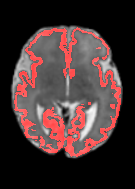

Fetal cortical plate segmentation is essential in quantitative analysis of fetal brain maturation and cortical folding. Manual segmentation of the cortical plate, or manual refinement of automatic segmentations is tedious and time-consuming. Automatic segmentation of the cortical plate, on the other hand, is challenged by the relatively low resolution of the reconstructed fetal brain MRI scans compared to the thin structure of the cortical plate, partial voluming, and the wide range of variations in the morphology of the cortical plate as the brain matures during gestation. To reduce the burden of manual refinement of segmentations, we have developed a new and powerful deep learning segmentation method. Our method exploits new deep attentive modules with mixed kernel convolutions within a fully convolutional neural network architecture that utilizes deep supervision and residual connections. We evaluated our method quantitatively based on several performance measures and expert evaluations. Results show that our method outperforms several state-of-the-art deep models for segmentation, as well as a state-of-the-art multi-atlas segmentation technique. We achieved average Dice similarity coefficient of 0.87, average Hausdorff distance of 0.96 mm, and average symmetric surface difference of 0.28 mm on reconstructed fetal brain MRI scans of fetuses scanned in the gestational age range of 16 to 39 weeks. With a computation time of less than 1 minute per fetal brain, our method can facilitate and accelerate large-scale studies on normal and altered fetal brain cortical maturation and folding.